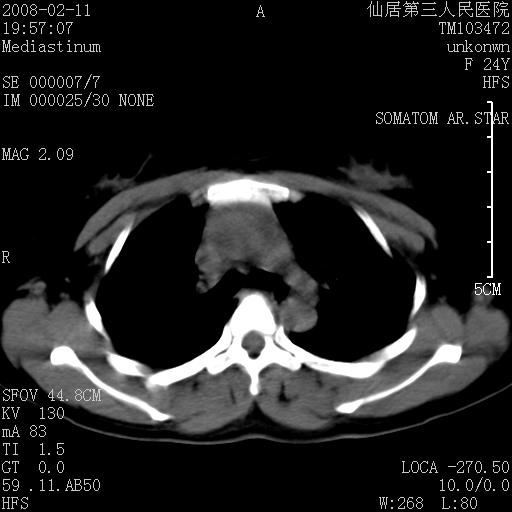

以下是引用zjzjr在2008-2-12 14:32:00的发言:[br]胸腺大点,是不是胸腺瘤或胸腺增生